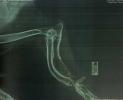

9. CD-диски с рентгенограммами двух щенков из помета.

В процессе выполнения работы эксперты столкнулись с рядом методологических сложностей. Одной из них была необходимость ретроспективного анализа состояния здоровья животного на основе доступной документации, поскольку первое рентгенологическое исследование было проведено лишь в пятимесячном возрасте, тогда как для точного определения момента формирования патологии "раннее закрытие дистальной ростковой зоны" требовались бы снимки, сделанные в динамике с 3,5 до 18 месяцев. Были тщательно проанализированы выписки из историй болезни двух щенков из одного помета, что позволило выявить схожесть патологий и оценить вероятность генетической предрасположенности. Применялись специализированные методики анализа рентгенографических изображений для оценки состояния костных структур, роста и окостенения суставных зон. Исследование проводилось с учетом положений Федерального закона «О ветеринарии» и «Об ответственном обращении с животными», а также актов кинологических организаций, таких как Положение РКФ о племенной работе. Были использованы данные ведущими научных источников по ветеринарной анатомии, ортопедии и физиологии, включая работы по дисплазии суставов и болезням опорно-двигательного аппарата у собак крупных пород. Особое внимание уделялось интерпретации изменений в костных структурах, таких как вальгусная деформация и особенности окостенения ростковых зон, а также их связи с быстрыми темпами роста, характерными для молодых животных крупных пород. Эксперты также изучали влияние потенциальных факторов содержания и питания, упомянутых в материалах дела, на развитие заболевания. Для достижения объективности и полноты заключения, каждый аспект дела был рассмотрен через призму актуальных ветеринарных и кинологических стандартов, обеспечивая всестороннюю оценку состояния здоровья щенка и его генетической предрасположенности.

1. Определить, в какой период времени сформировалось у щенка заболевание – раннее закрытие дистальной ростковой зоны правой лучевой кости – до 22.03.2018 или после 22.03.2018.